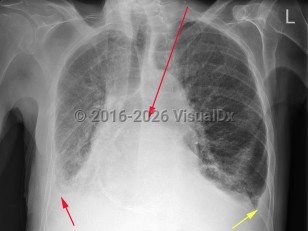

Congestive heart failureCongestive heart failure

Pulmonary hypertension

Pulmonary embolismPulmonary embolism

SarcoidosisSarcoidosis